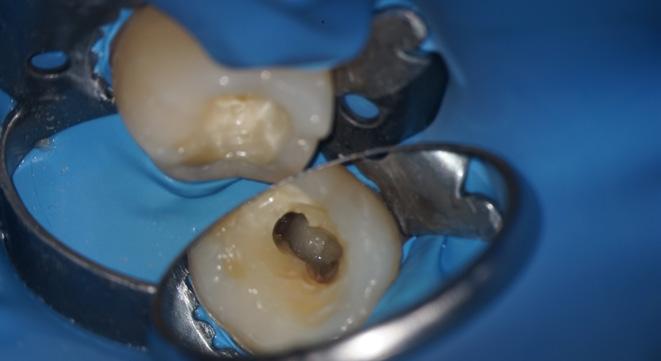

One of the suitable indications for FRC is the endodontically treated premolar with one big orifice and one large oval canal or deep furcation (Figs. 1-4). In such cases, an FRC can be placed as a Nayyar’s core modification5 without preparing the orifice part with Gates or Largos. The restoration can be finished as usual, directly with a conventional composite.

Fig. 2: A free space with a depth of 3-4 mm was created in the orifice part with a heated plugger.

Fig. 3: The proximal wall was created first using a conventional composite. The core was built up with everX Flow (GC), a flowable fibre-reinforced composite